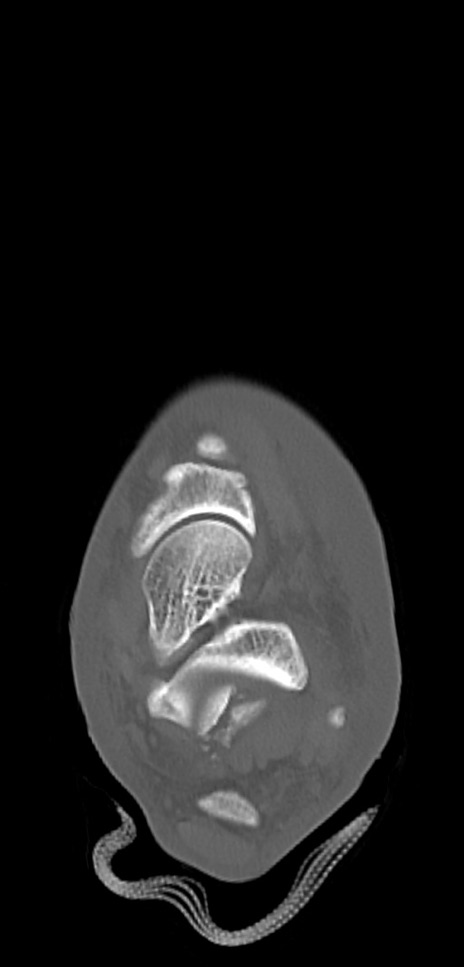

症例37 左足関節CT(横断像)

左足関節CT